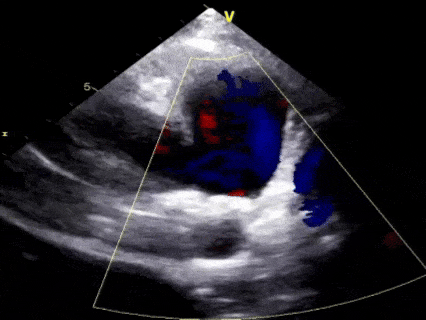

术后6个月随访

无残余分流,封堵效果良好

本病例为一例9岁患儿,超声心动图检查显示为典型的漏斗型PDA,肺动脉侧内径4mm,主动脉侧内径7mm;鉴于患儿处于重要生长发育阶段,术中选择全降解封堵器联合纯超声引导的治疗方案,选用经股动脉途径进行介入封堵,既通过可降解材料避免金属永久存留,又完全规避X线辐射风险。本例手术经股动脉路径植入全降解封堵器(腰高5mm、腰部直径9mm),严格遵循“一贴二扣三锁四剪五撤”的5S规范化操作,超声影像清晰地观察到封堵器的释放过程及其与PDA的贴合情况,术后即刻评估显示封堵效果理想,无任何残余分流。术后3个月及6个月随访均无残余分流,封堵效果良好。